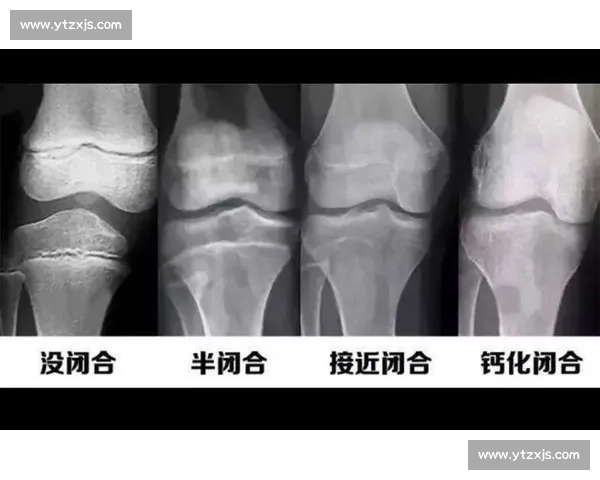

- 骨龄检测:建议先到三甲医院进行左手腕 X 光片检查,通过 Greulich-Pyle 图谱评估骨龄。若骨骺线未闭合,可在医生指导下进行生长激素激发试验。